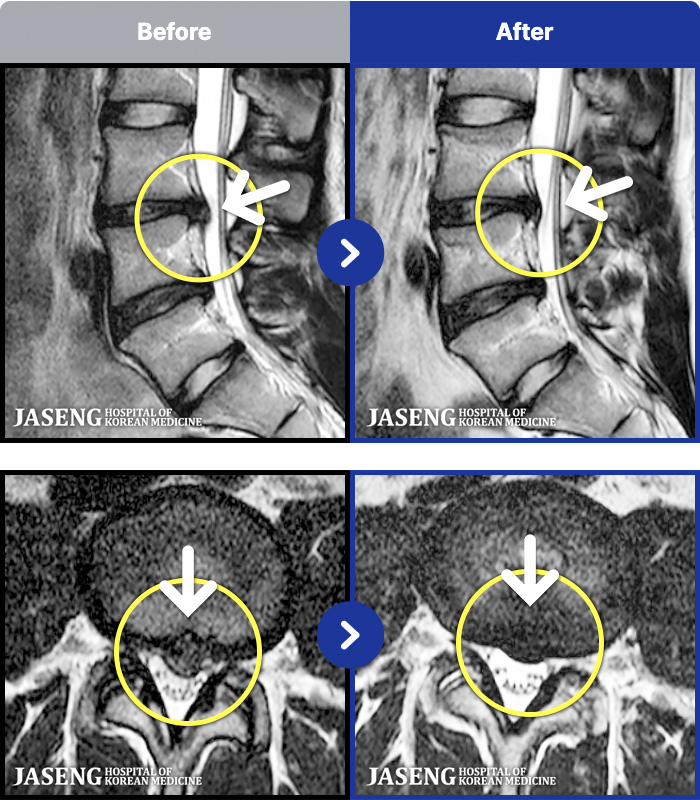

1,286 MRI ũ ʸ Ȯϼ.